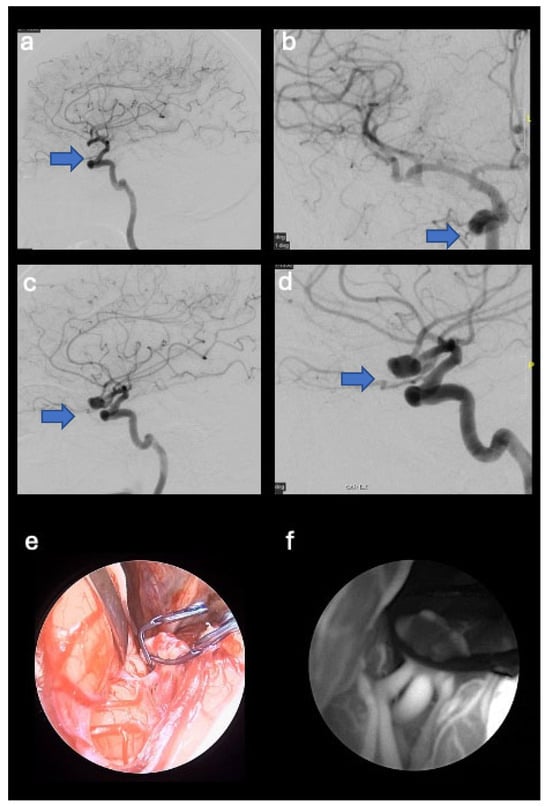

- A 44-year-old female patient with a right middle cerebral artery aneurysm (M1-M2 union) with a diameter of 1 cm, a history of headaches. The patient underwent clipping of the aneurysm neck (see Figure 2).

3.2.2. CASE Number 4

| 4 | 44 | F | Headache | Right middle cerebral artery aneurysm (M1-M2 union) with a diameter of 1.1 cm | Clipping of the aneurysm neck | Neurologically intact, total exclusion of the aneurysm, and no bleeding events. |